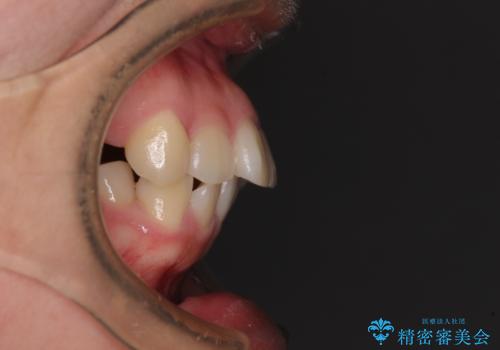

地元で矯正治療を始める予定で上顎左右第1小臼歯2本を抜歯したものの、その後転居したため治療が滞っているとのことでした。

上下ともに歯列が前方に突出していたため、上下左右の第一小臼歯4本を抜去する方針(既に上顎は抜歯されています)で、ワイヤー装置による矯正治療を行うこととしました。

舌の突出癖による影響もあったため、舌のトレーニングを並行して実施しました。